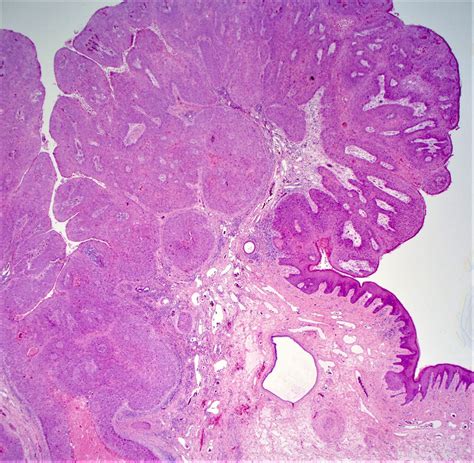

Thrombosed Piles Images: A Visual Guide

Visual aids can be invaluable in understanding and diagnosing thrombosed piles. Thrombosed piles images can help individuals recognize the signs and symptoms of this condition. Below is a table highlighting key visual indicators:

Visual Indicator Description

Swelling A noticeable lump or swelling around the anus.

Discoloration The affected area may appear blue or purple.

Redness The skin around the anus may be red and irritated.

Bleeding Small amounts of blood may be visible on toilet paper or in the stool.

Recognizing these visual indicators can help individuals seek timely medical attention and improve the chances of successful treatment.

Thrombosed Piles Images